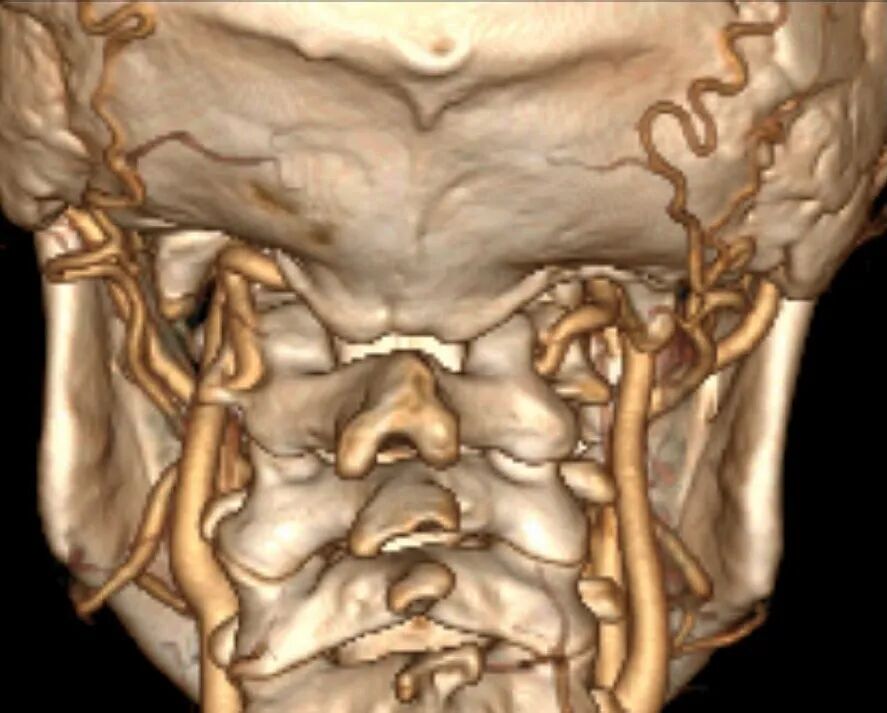

寰枢椎由3个关节构成:正中寰齿关节,两侧侧方关节。大多数寰枢椎脱位患者,特别是颅底凹陷合并的寰枢椎脱位患者,寰枢椎关节存在严重畸形,畸形的关节突发生严重的绞锁(图1),这导致寰枢椎脱位复位具有很大难度[1, 2]。

颅颈交界区骨性结构畸形常常伴有椎动脉走行异常,特别是寰枕融合畸形。当寰枕融合畸形发生时,寰椎后弓、两侧侧块、横突与枕骨融合消失,导致椎动脉V3段穿过枢椎横突孔后便失去了寰椎横突孔和寰椎后弓等骨性结构的引导,进而出现走行异常,椎动脉直接向内侧跨过枢椎椎弓峡部进入椎管。椎动脉V3段走行异常会遮挡寰枢椎关节面的后方(图8),增加了从后路在进行寰枢椎关节间操作和寰枢椎椎弓根置钉过程中损伤椎动脉的风险。